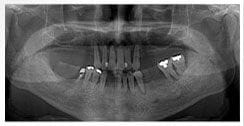

X 光片

術前X光片

術後X光片